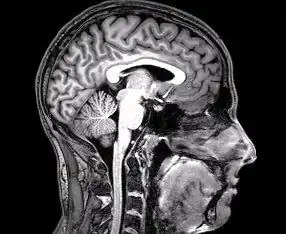

Cerebro humano

- ↑ Del Proyecto "Humano Visible" (Visible Human Project de la Biblioteca Nacional de Medicina de Estados Unidos. En este proyecto, dos cadáveres humanos (de un hombre y una mujer) fueron congelados y luego cortados en láminas delgadas, que fueron fotografiadas y digitalizadas individualmente. Esta sección está tomada a una pequeña distancia de la parte superior del cerebro, y muestra la corteza cerebral (la capa celular plegada al exterior) y la sustancia blanca subyacente, que consiste en tramos de fibra mielinizada que viaja hacia y desde la corteza cerebral.